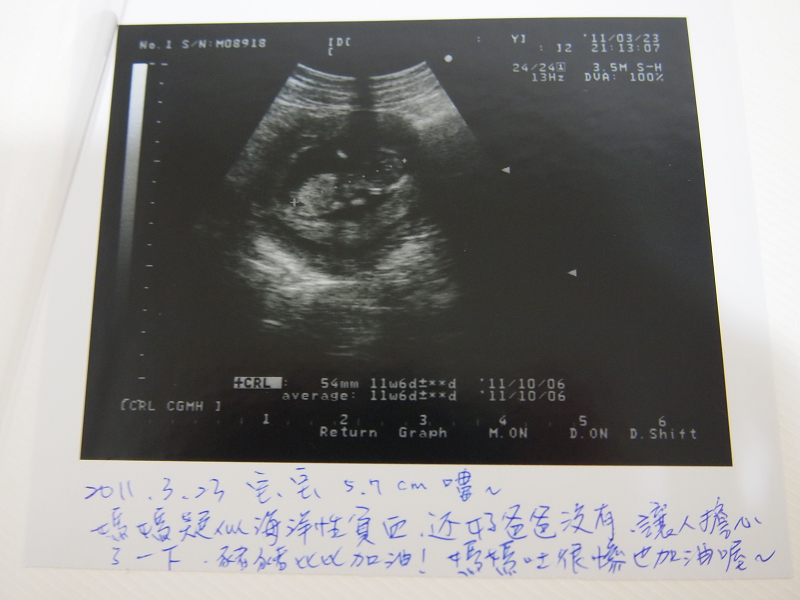

看完醫生 醫生馬上下達指令要住院 鼻過比比看起來也ok~